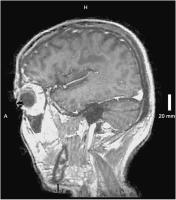

Abbildung 4: Spinale T1-TSE sagittal: Atrophie des gesamten Myelons.

Keywords:

Adrenomyeloneuropathie

,

Atrophie

MRT

Myelom

Neurologie